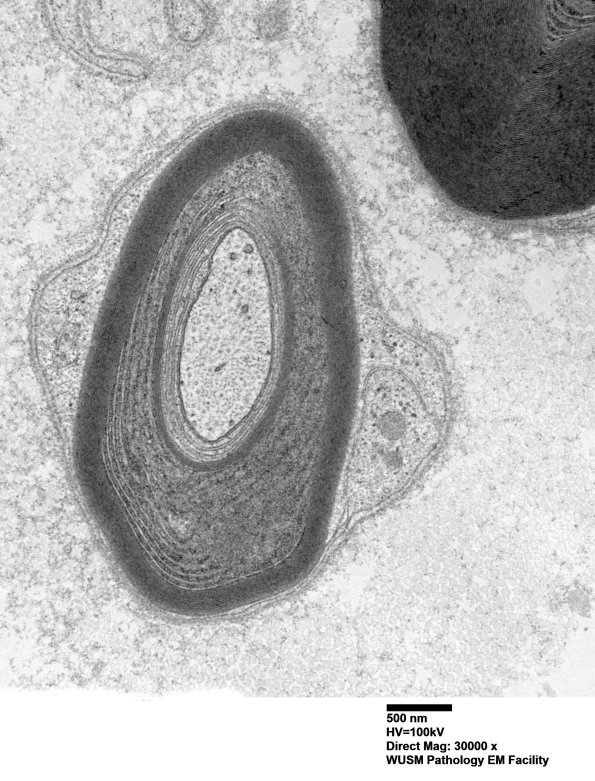

Washington University Experience | PERIPHERAL NEUROPATHY | 13 POEMS SYNDROME | 1B2B (Case 1) Sural_036 - Copy

1B2B,C In some cases the angle of section hides the lamellar change. (electron micrographs)